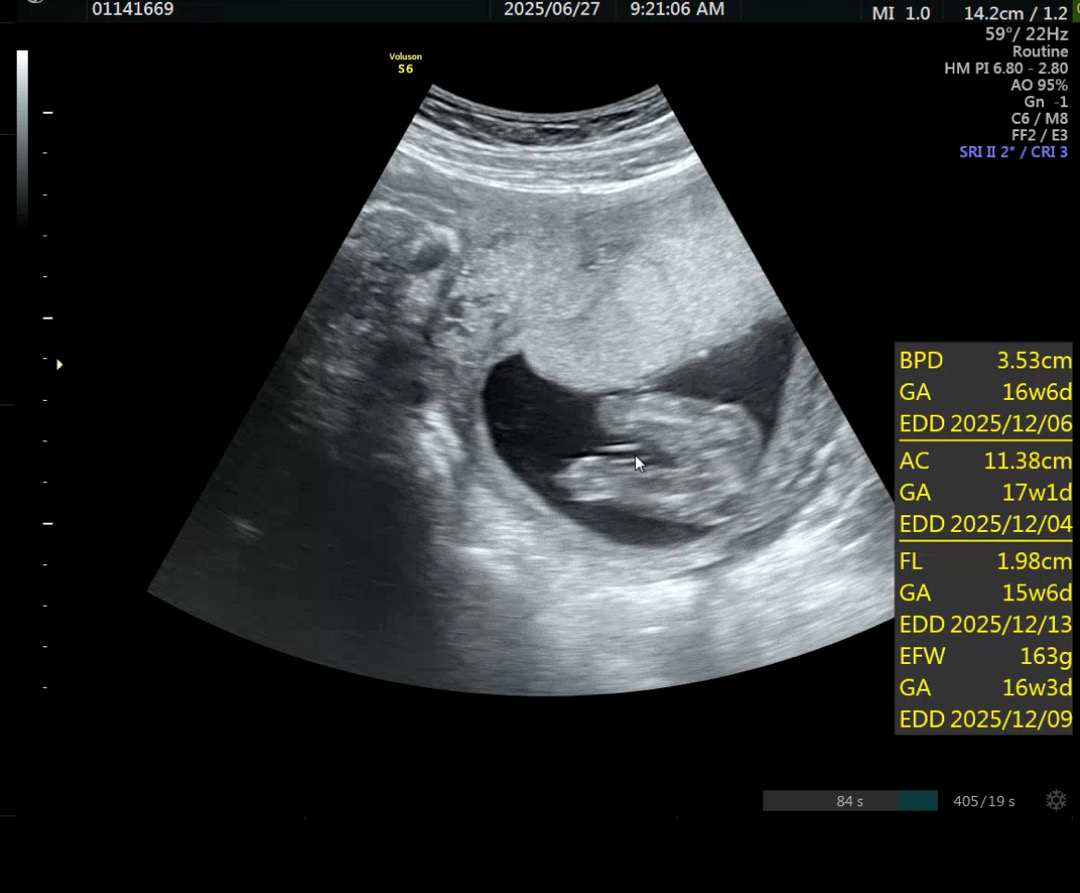

1차 기형아 검사 하고, 한 달 만의 병원 방문이라 이제쯤 성별을 볼 수 있겠구나 생각하며 기대하고 갔는데 제가 다니는 병원이 큰 병원이다 보니 초음파도 짧게 봐주시고 자세가 성별 알 수 있는 자세가 아니라 하고 다음에 봅시다 하고 마시더라구요 ㅜㅜ 아쉬운 마음이 너무 큰데 사진 한 번 봐주실 수 있나요. 오늘 자로 16주 6일 입니다. 저기 마우스 커서 두신 게 탯줄이라고 하시더라구요.

짧아도 bpd fl ac efw처럼 이거저거 봐주셨네용..🫢 저는 12주 니프티하고 4주만의 방문이었는데, bpd만 재고 옆모습 보고 심장 박동만 듣고 와서 "이번에는 왜 몸길이 안재주시는거지..?"했네요😭 기다린거에 비해 너무 짧은 시간 초음파 보는 느낌..암튼 좋은 생각하고 맛있는거 먹고 건강한 아이 낳읍시당☺️